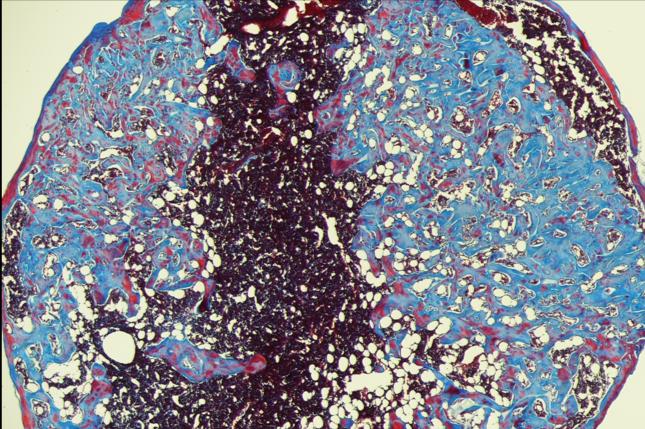

Drawing upon the Mooney Lab's pioneering research in the development of biomaterials for providing cell-instructive cues, the researchers engineered a sponge-like cell factory, with large pores that allows cells to move in and out. The sponge has two built-in proteins, one that recruits outside cells and the other to create the T-cell progenitors. The first, called bone morphogenetic protein 2, recruits local cells and encourages them to become bone cells. Once the sponge resembles vascularized bone marrow, the second protein encourages the blood stem cells living in the device to produce T-cell progenitors.

When the researchers tested the device in mice receiving a hematopoietic stem cell transplant, they found that the mice treated with the scaffold generated T-cells faster when compared with mice that did not.